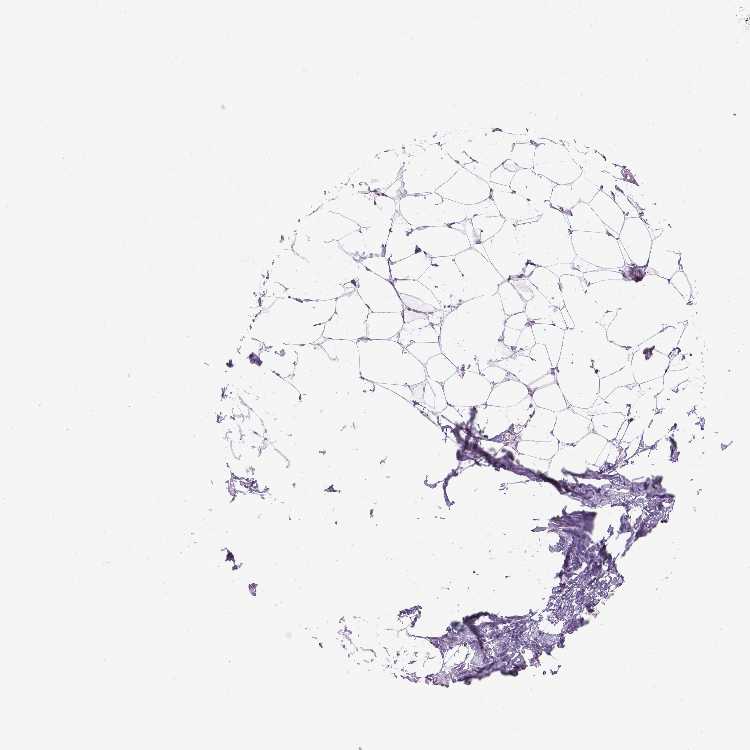

BREAST - Antibody stainingi

Antibody staining in the annotated cell types in the current human tissue is reported as not detected, low, medium, or high, based on conventional immunohistochemistry profiling in selected tissues. This score is based on the combination of the staining intensity and fraction of stained cells.

Each image is clickable and will lead to virtual microscopy that enables deeper exploration of all samples and also displays staining intensity scores, fraction scores and subcellular localization as well as patient and tissue information for each sample.

Antibody HPA070314

Adipocytes Not detected

Glandular cells Not detected

Myoepithelial cells Not detected